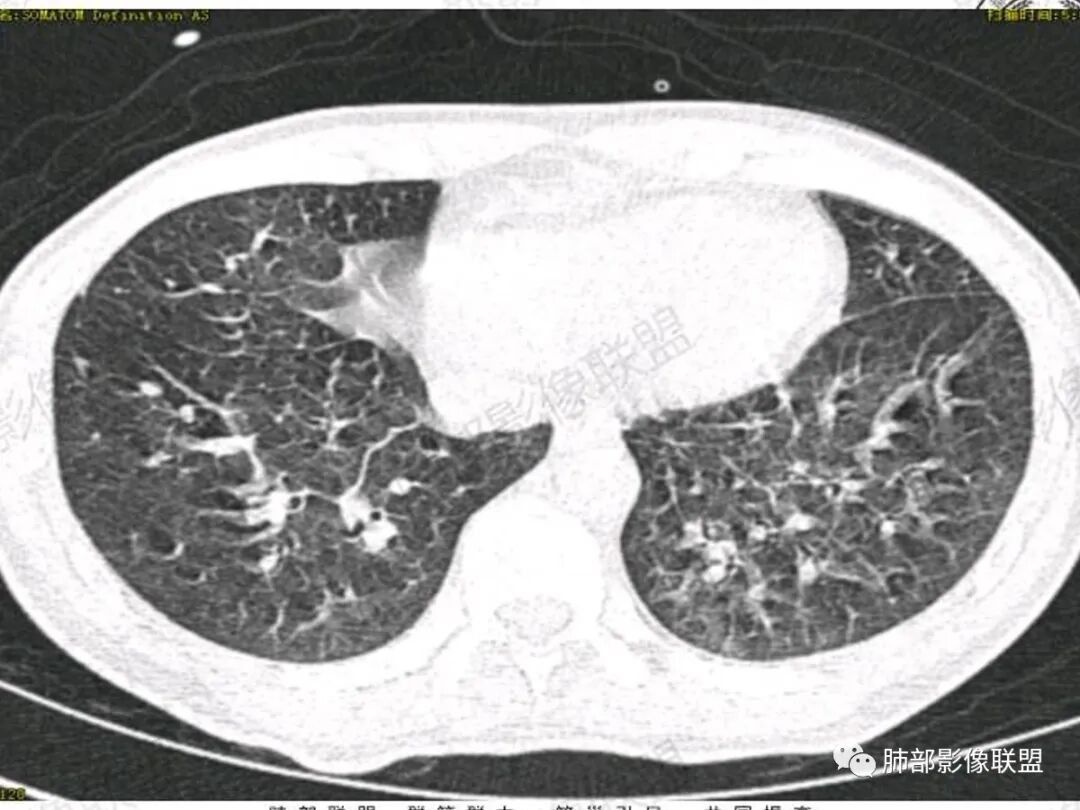

双肺上叶,下叶背段多发斑片状实变影,以胸膜下分布为主,部分重力作用,以背侧为主,部分小叶间质增厚,部分周围伴有散在磨玻璃影,边界欠清,临床急性病程,血象增及PCT明显增高,意识模糊,考虑:吸入性肺炎?鉴别:AHP?CEP?PCP

影像:两肺上叶小叶间隔增厚,斑片,腺泡结节,重力分布,下肺不累及

影像学提示肺水肿与肺泡腔液性渗出(小叶间隔增厚+实变+重力趋势),上叶显著。

双肺弥漫性病变以上肺,向心性,背部分布为主,肺动脉干无增粗,急性起病,典型的吸入性肺炎。

青年男性,气促7小时入院,意识模糊,白细胞及中性粒明显增高,PCT增高,CRP不高,心率快,体温正常,血压正常。胸部CT:双肺上叶小叶间隔光滑增厚,中轴间质增厚,弥漫性磨玻璃、多发斑片影,以上肺、背侧分布为主。影像表现考虑为肺水肿。病因:病史不支持肾功能衰竭、心源性、高原性肺水肿,无发热,似乎也不支持细菌、病毒、真菌等感染引起。吸入毒物?吸入水?

病灶的分布以上肺为主

确实要考虑吸入,倾向于吸入的是气体类的可能,因为朝上走

结合病史,最终诊断是 “急性烟雾吸入性肺损伤”,影像学表现主要是肺水肿及弥漫性肺泡损伤改变,因为烟雾气体吸入肺内分布以上肺显著,因此影像学表现也是累及上肺更明显。损伤因素包括大量一氧化碳 二氧化碳 一氧化氮等燃烧产生的有毒气体,也有烟雾粉尘颗粒对气道黏膜的损伤。